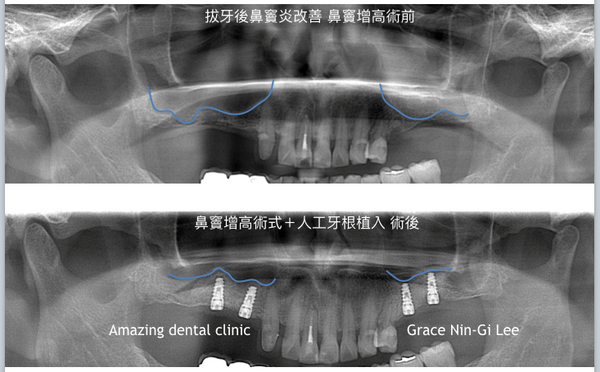

首先初診,病人右上方斷裂殘根已經感染至鼻竇炎.拔除殘根後,慢性鼻竇炎因為移除感染源而經耳鼻喉科醫師確診康復.

因為多年缺牙,鼻竇氣化得太嚴重了,只剩下約莫2毫米的骨頭.手術以鼻竇側方骨性開窗方式,保留鼻竇膜schneiderian membranes完整性,以人工骨粉將增加骨質空間至14毫米以上,開窗骨版折入鼻竇內部,開窗處以可吸收再生膜覆蓋後縫合.